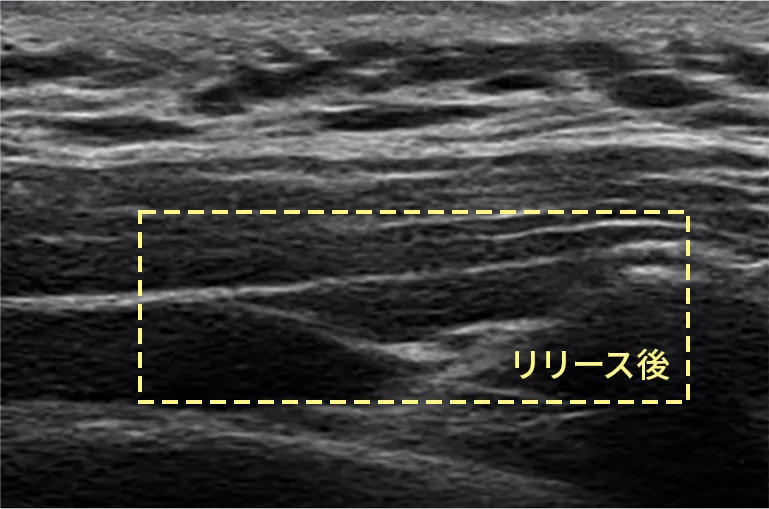

筋膜リリース注射の仕組み

• 筋膜リリース注射後 筋膜リリース注射後のエコー写真

筋膜リリース注射 エコー動画

当院では肩こりの原因に直接アプローチできる注射による筋膜リリース(ハイドロリリース)を行っています。超音波装置を使用して、実際に筋膜が剥がれていく様子を目で見て確認しながら治療をします。この直達的な手技により マッサージでは行えない筋膜リリースが可能です。

そこで、 エコーを見ながら針と液体(生理的食塩水)を用いて、直接的に膜を剥がしていくのです。これを筋膜リリース(ハイドロリリース)注射と呼びます。